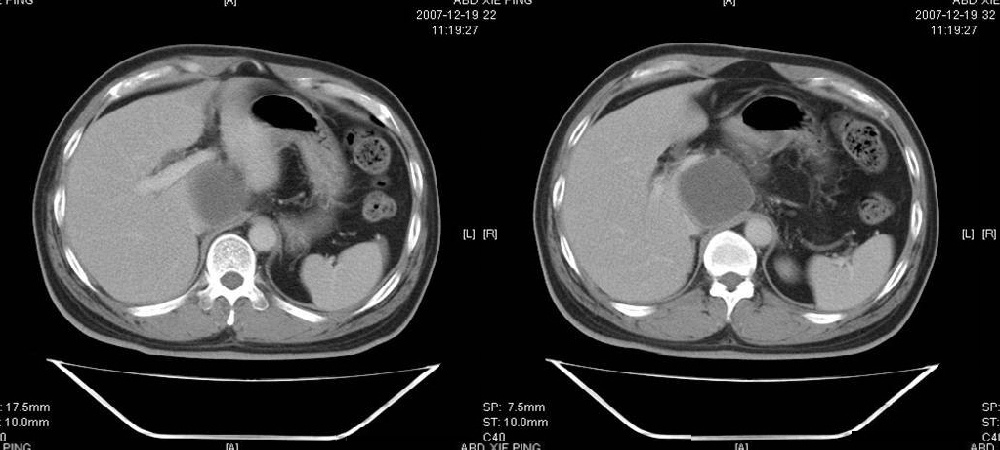

临床病史:患者,男,53岁,因反复上腹部饱胀不适2+月,在餐后或饥饿时明显,伴呃逆,无呕吐、呕血,无腹痛腹泻;2年前腹腔镜胆囊切除,否认肝炎、结核等病史。

体格检查:一般情况可,腹平软,全腹无压痛,无反跳痛,未扪及包块,肝脾未及,肠鸣音正常。白细胞6.03×10e9/l,中性粒细胞3.32×10e9/l,淋巴细胞2.06×10e9/l

胰腺头部低密度囊性病灶,边缘清楚,增强后囊壁略强化。考虑:胰头假性囊肿!

胰腺头部(或肝脏尾叶部)低密度囊性病灶,边缘清楚,增强后囊壁略强化。考虑:胰头假性囊肿. 或肝脏尾叶部囊肿。

考虑十二指肠憩室。从影像上看,病变位于下腔静脉前胰头后方十二指肠内侧,肝尾叶受压,说明病变来源于后腹膜;胰胆管成像胰管和胆道未见扩张,总胆管中段受压未显示,上下段正常,所以不考虑来源与于肝尾叶和总胆管的囊肿。考虑为十二指肠憩室或小网膜囊肿。

楼上高手,本例的确是一例十二指肠憩室.